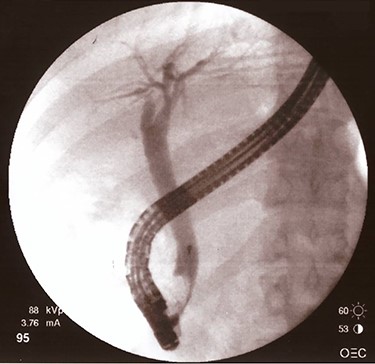

After 40 days, patient had no signs of liver and biliary complications and kehr’s tube appeared normally placed. Blood count and bilirubin was normal with alkaline phosphatase 447 U/l, AST 112 U/l, ALT 162 U/l. Trans-kehr cholangiography showed normal size of CBD (Fig. 3), so it was removed and replaced with a single plastic biliary stent (9-cm length and 10-Fr diameter) through an ERCP.